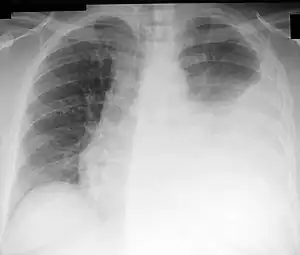

| Chest X-ray showing a left-sided pleural effusion (right side of image) that was than treated with thoracentesis. | |